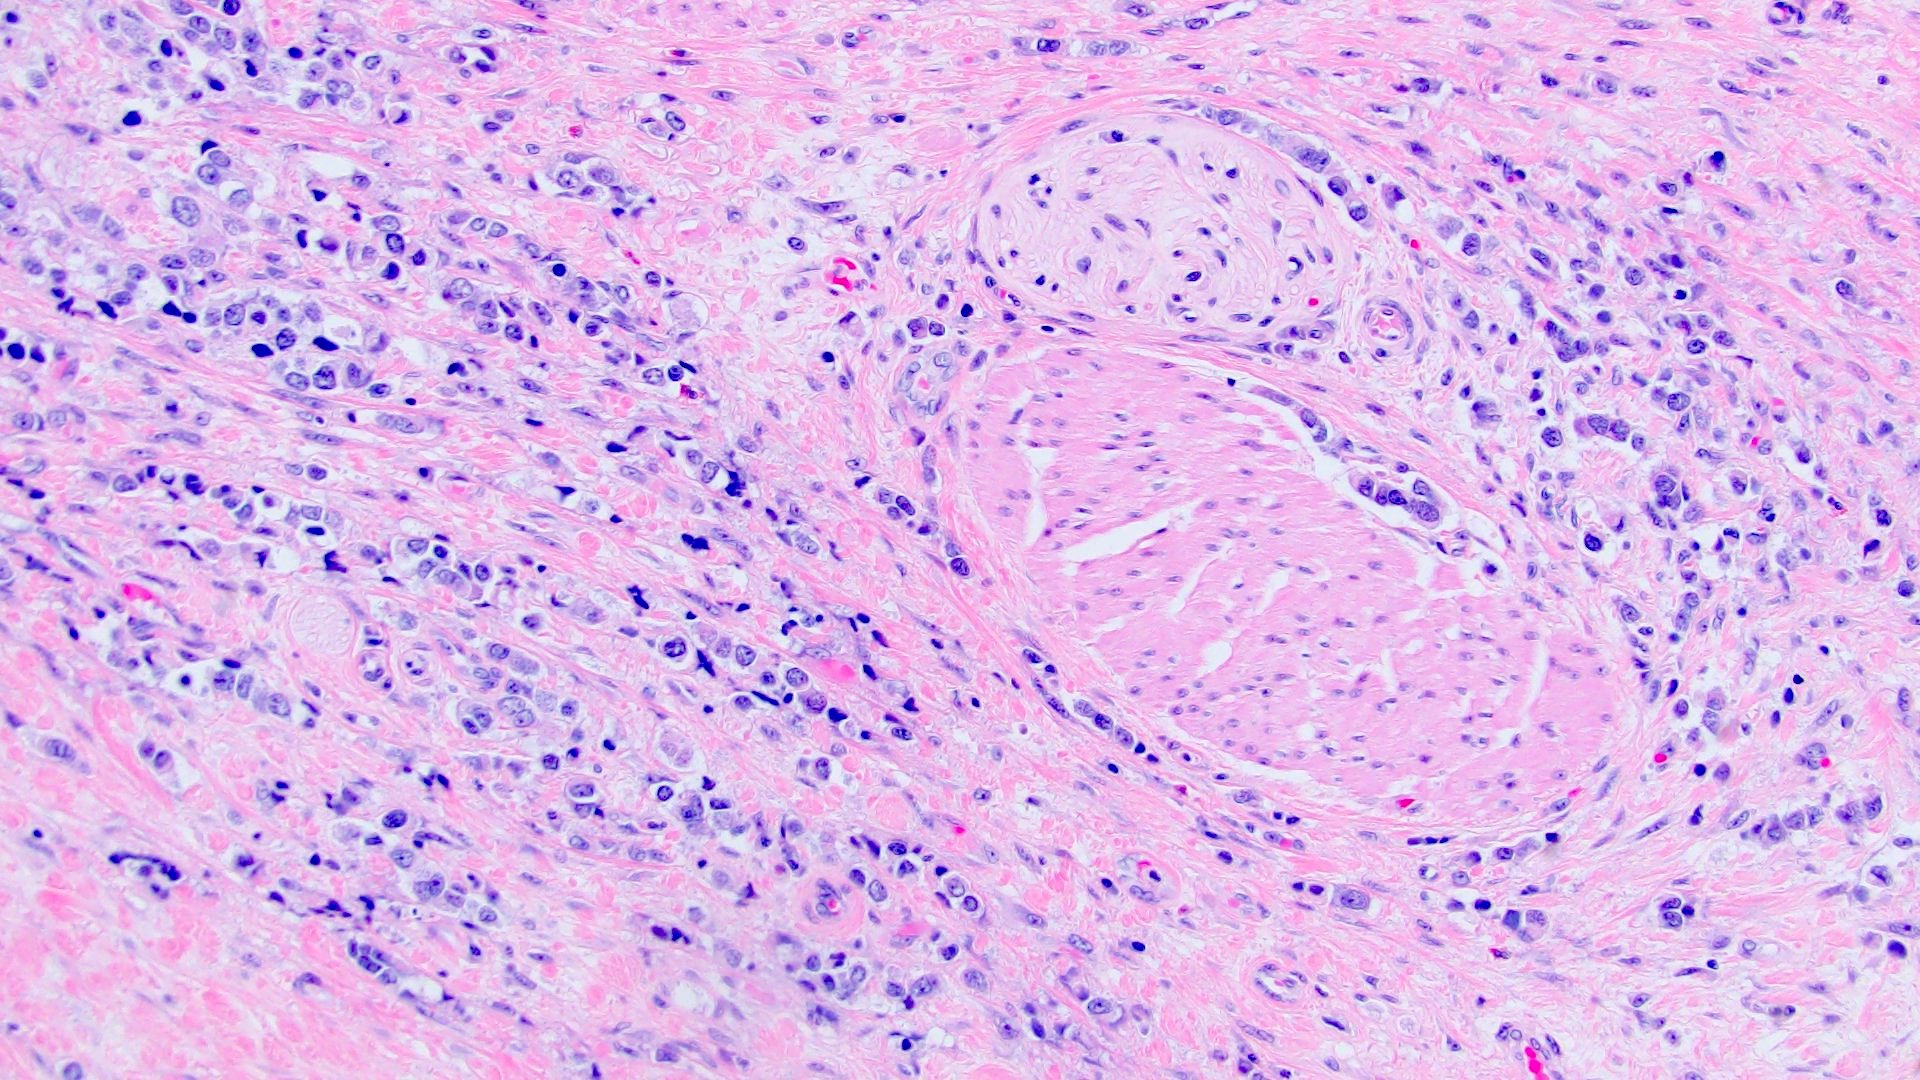

Microscopic (histologic) description

- Discohesive single cells with eccentrically placed nuclei and abundant eosinophilic cytoplasm

- Often deeply infiltrative but with minimal stromal reaction (Eur Urol Focus 2020;6:653)

- Further subclassified into classic, pleomorphic and desmoplastic subtypes:

- Classic: signet ring-like morphology, singly scattered and discohesive in loose aggregates forming cords (Hum Pathol 2019;90:27)

- Pleomorphic: similar to classic but with pleomorphic nuclei and more atypia; can be rhabdoid and bizarre appearing (Hum Pathol 2019;90:27)

- Desmoplastic: plasmacytoid neoplastic cells with a surrounding desmoplastic stromal response (Hum Pathol 2019;90:27)

- Associated with sarcomatoid variant in 31% of cases (Hum Pathol 2019;90:27)

- Often mixed with other histologic subtypes; in 1 case series, 53% of PUC had mixed histologic subtypes (Am J Clin Pathol 2017;147:500)

- Despite resemblance to signet ring carcinoma cells, notably lack extracellular mucin, contrasting to signet ring adenocarcinoma (Acta Cytol 1991;35:277, Am J Surg Pathol 1991;15:569)

Microscopic (histologic) images

Contributed by Timothy Isaac Miller, M.D., M.A., Nicole K. Andeen, M.D. and Maria Tretiakova, M.D., Ph.D.